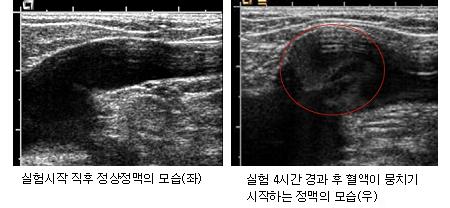

ÃÖ±Ù ´ëÇÑ¿µ»óÀÇÇÐȸ°¡ ºñÇà±â ÀϹݼ®°ú °°Àº ȯ°æ¿¡¼­ 20´ë ÃÊ¹Ý ³²¼ºÀÇ ½ÇÁ¦ Ç÷·ù¼Óµµ¸¦ ÃøÁ¤ÇÑ °á°ú, 4½Ã°£ °æ°ú ÈÄ Ç÷¾×ÀÌ ³óÃàµÇ¸é¼­ Ç÷·ù¼Óµµ°¡ ½É°¢ÇÏ°Ô ÀúÇϵƴÙ. 6½Ã°£ÀÌ Áö³­ ÈÄ¿¡´Â Ç÷·ù¼Óµµ°¡ ±Þ°ÝÈ÷ ´À·ÁÁö°í ½ÉÁö¾î Ç÷¾×ÀÌ ¿ª·ùÇÏ´Â µî Ç÷Àü(ÇǶ±) Çü¼ºÀÇ ÀüÁ¶ Áõ»óÀÌ ³ªÅ¸³µ´Ù.